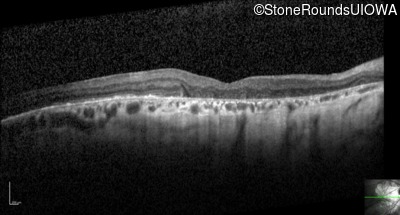

Optical Coherence Tomography - Right - 20/100 +1

Exemplar / OCT Stack